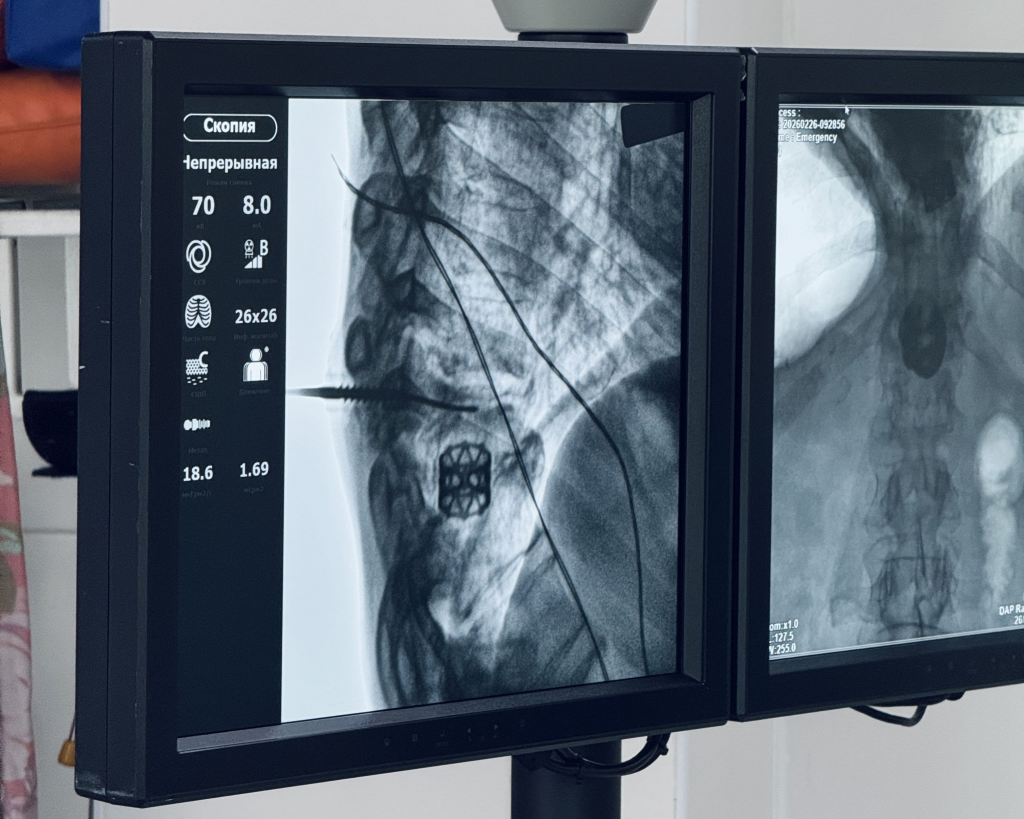

Нейрохирурги Свердловского областного клинического психоневрологического госпиталя для ветеранов войн вернули 73-летнему мужчине возможность жить без боли. В ходе малоинвазивного вмешательства специалисты учреждения здравоохранения выполнили пациенту фиксацию позвоночника, деформация которого была осложнена хронической инфекцией. Спасительным решением стала отечественная разработка, не уступающая мировым аналогам.

Обследование подтвердило воспалительное поражение межпозвонковых дисков, которое привело к нарушению оси позвоночника и его выраженной деформации. Ключевой задачей для нейрохирургов стал выбор метода, который одновременно обеспечил бы надёжную стабилизацию позвоночника и исключил риск распространения инфекции. Чтобы помочь пациенту, специалисты использовали отечественную систему: её полые внутри винты устанавливаются по тонкой направляющей спице, обеспечивая точность позиционирования имплантов и минимальное повреждение мягких тканей.